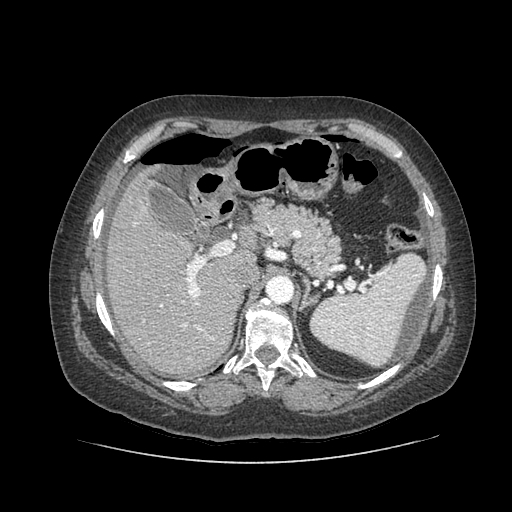

Pneumoperitoneum (PP) in peritoneal dialysis (PD) patients is a rare complication; however it should be considered to avoid an unnecessary laparotomy and that will also compromise the dialytic options. A 70 year-old woman with end-stage renal disease had been on chronic PD with automated night therapy for 21 months, without complications or any signs of peritonitis. She was admitted with a sudden epigastric pain. Tympanic abdomen was present on physical examination. The Tenckhoff catheter exit site looked unremarkable. Laboratory testing showed a normal white cell count. An important PP was visible in chest and abdominal X-rays. Contrast-enhanced abdominal CT scan confirmed a generalised PP distributed in supramesocolic recesses. No extravasation of endoluminal contrast was seen. Dialysis catheter was placed at left lower quadrant. We performed the aspiration of PP using an aseptic technique in Trendelenburg position. Abdominal X-ray showed resolution of PP. In the following day she was asymptomatic but abdominal X-ray revealed a newly developed PP, thus we decided to remove the catheter with no recurrence of PP.Downloads